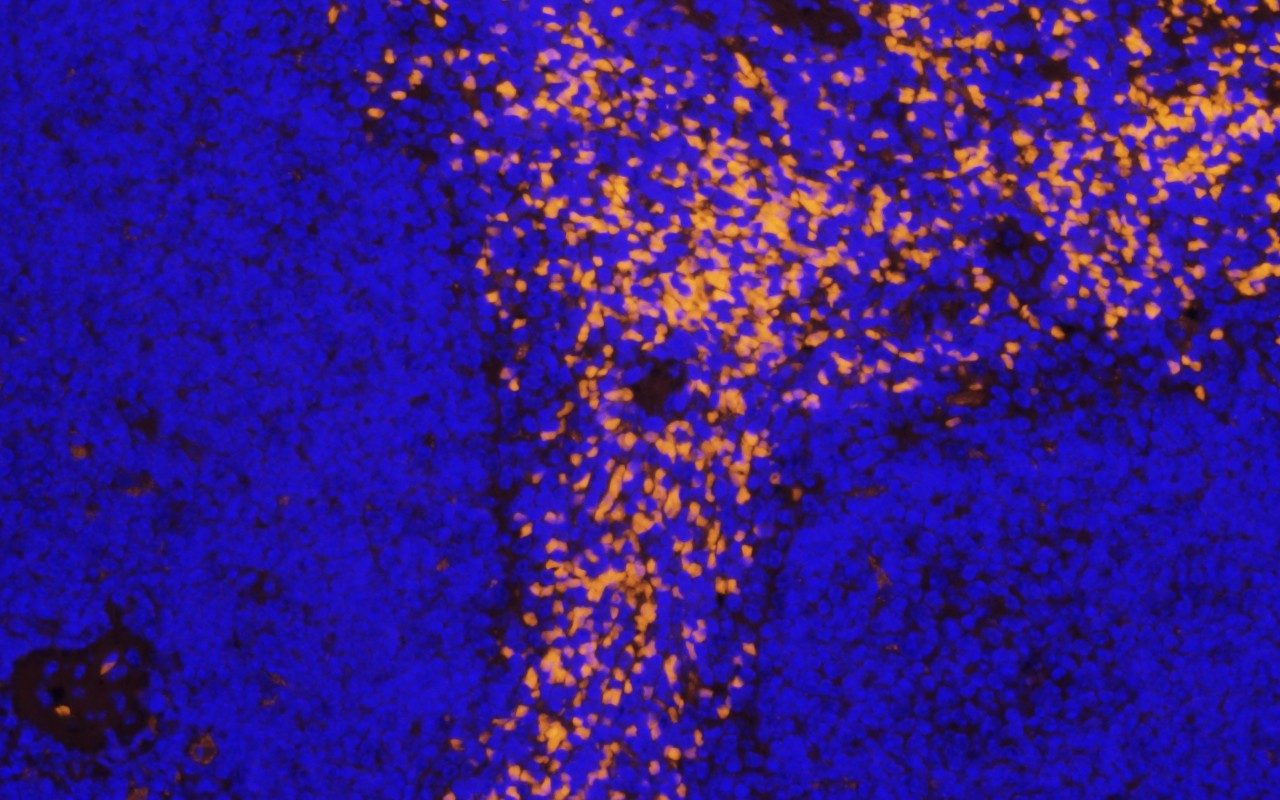

- Multiplex Immunofluorescence

Digital Pathology includes quantification and annotation, which will be offered in conjunction with whole slide scanning using our Aperio AT2 slide scanner. The RHCL can provide automated quantification (upon request) for accurate evaluation of complex staining patterns which allows researchers and clinicians to interpret tissue staining.

The Research Histology Core Laboratory (RHCL) offers Digital Pathology and Imaging services. Digital Pathology includes Quantification and Annotation which will be offered in conjunction with slide scanning using our Leica Aperio AT2 Slide Scanner. Slide Scanning will provide automated quantification for accurate evaluation of complex staining patterns which allows researchers and clinicians to interpret tissue staining.